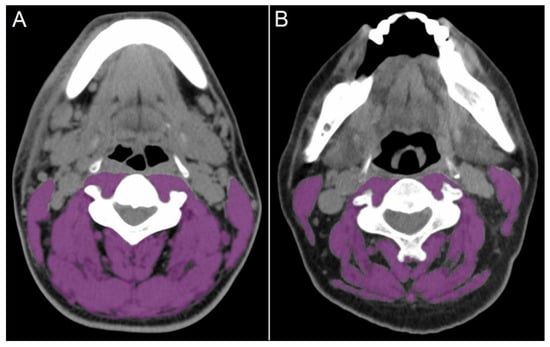

2.2. Definition of Sarcopenia, Frailty, and Inflammatory Status

Figure 1. Skeletal muscle area regions in computed tomography images at the third cervical vertebral level in patients without (A) and with (B) sarcopenia.